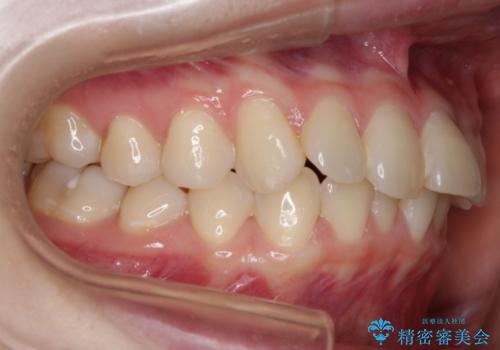

一見そこまで大きなガタつきはないようにも見えますが、前歯の角度の不揃いや噛み合わせのズレなどから見え方に影響が出てしまっていました。

抜歯は全く必要のないレベルのガタつきだったため、マイクロインプラントを用いて歯全体を後方に移動させていくことできれいな歯並びを獲得することができました。

マウスピースとマイクロインプラントを組み合わせることで、抜歯をしなくても歯並びを治すためのスペースを作ることができます。奥歯から順に移動させていくので前歯に変化が出るまでには時間がかかりますが、どの分健康な歯を抜歯することなく理想的な歯並びを手に入れることができます。